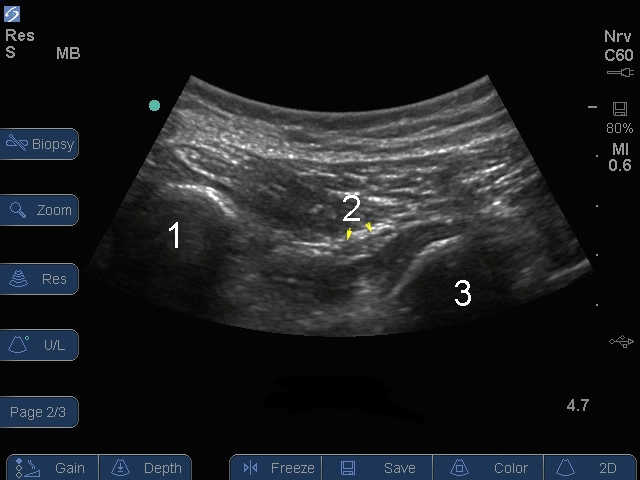

Bild: S Series, Nervus ischiadicus, gluteale Ebene

Tuber

Nerve (Nerv)

Trochanter major